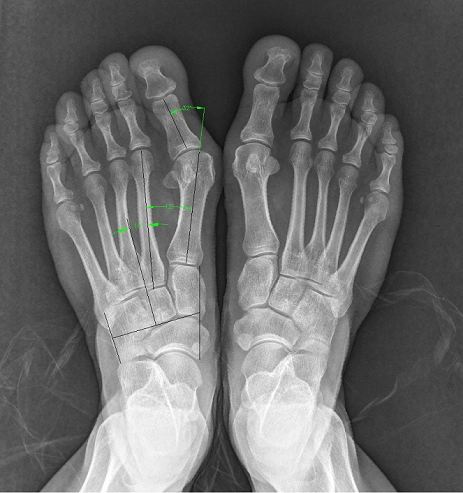

x光片更直观了解大脚骨 如果单纯去掉凸起能否有效矫正拇外翻呢?

对于重度拇外翻(拇外翻角大于40°,第1,2跖骨间夹角大于20°),除常规